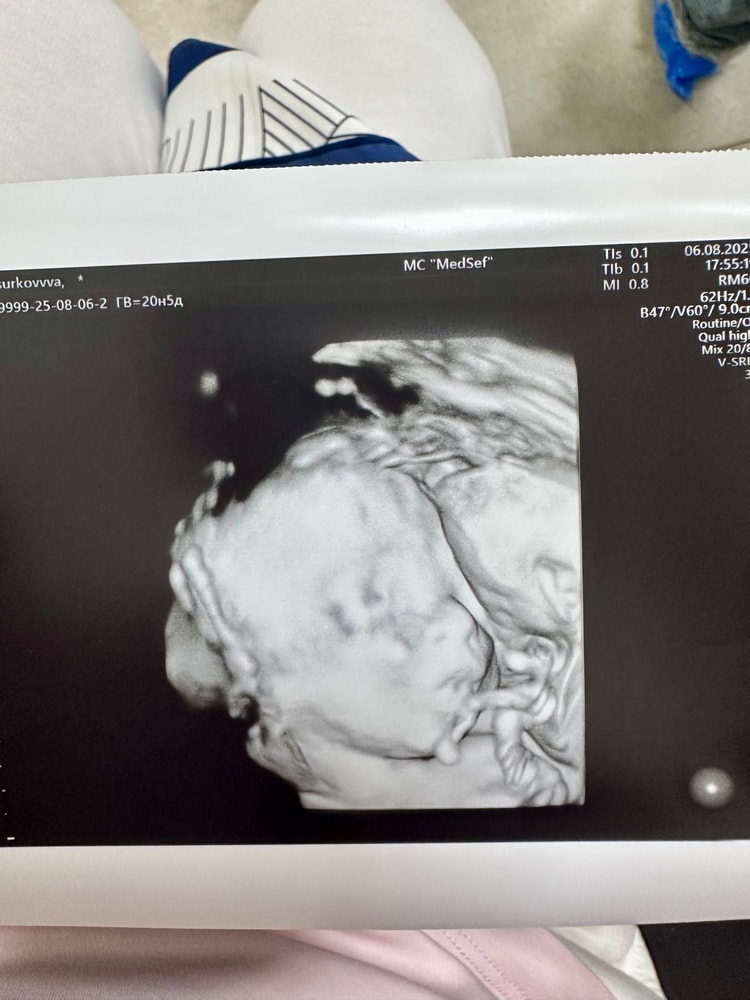

Девочки поделитесь весом своих малышей на сроке 30 недель. Вернулась сегодня с узи ,вес малышки 1457. Вот не пойму мало или в норме🙈. Расчитывала ,что будет побольше. Хотя врач сказала ,что все в порядке. Но моя голова что-то ищет подвох.